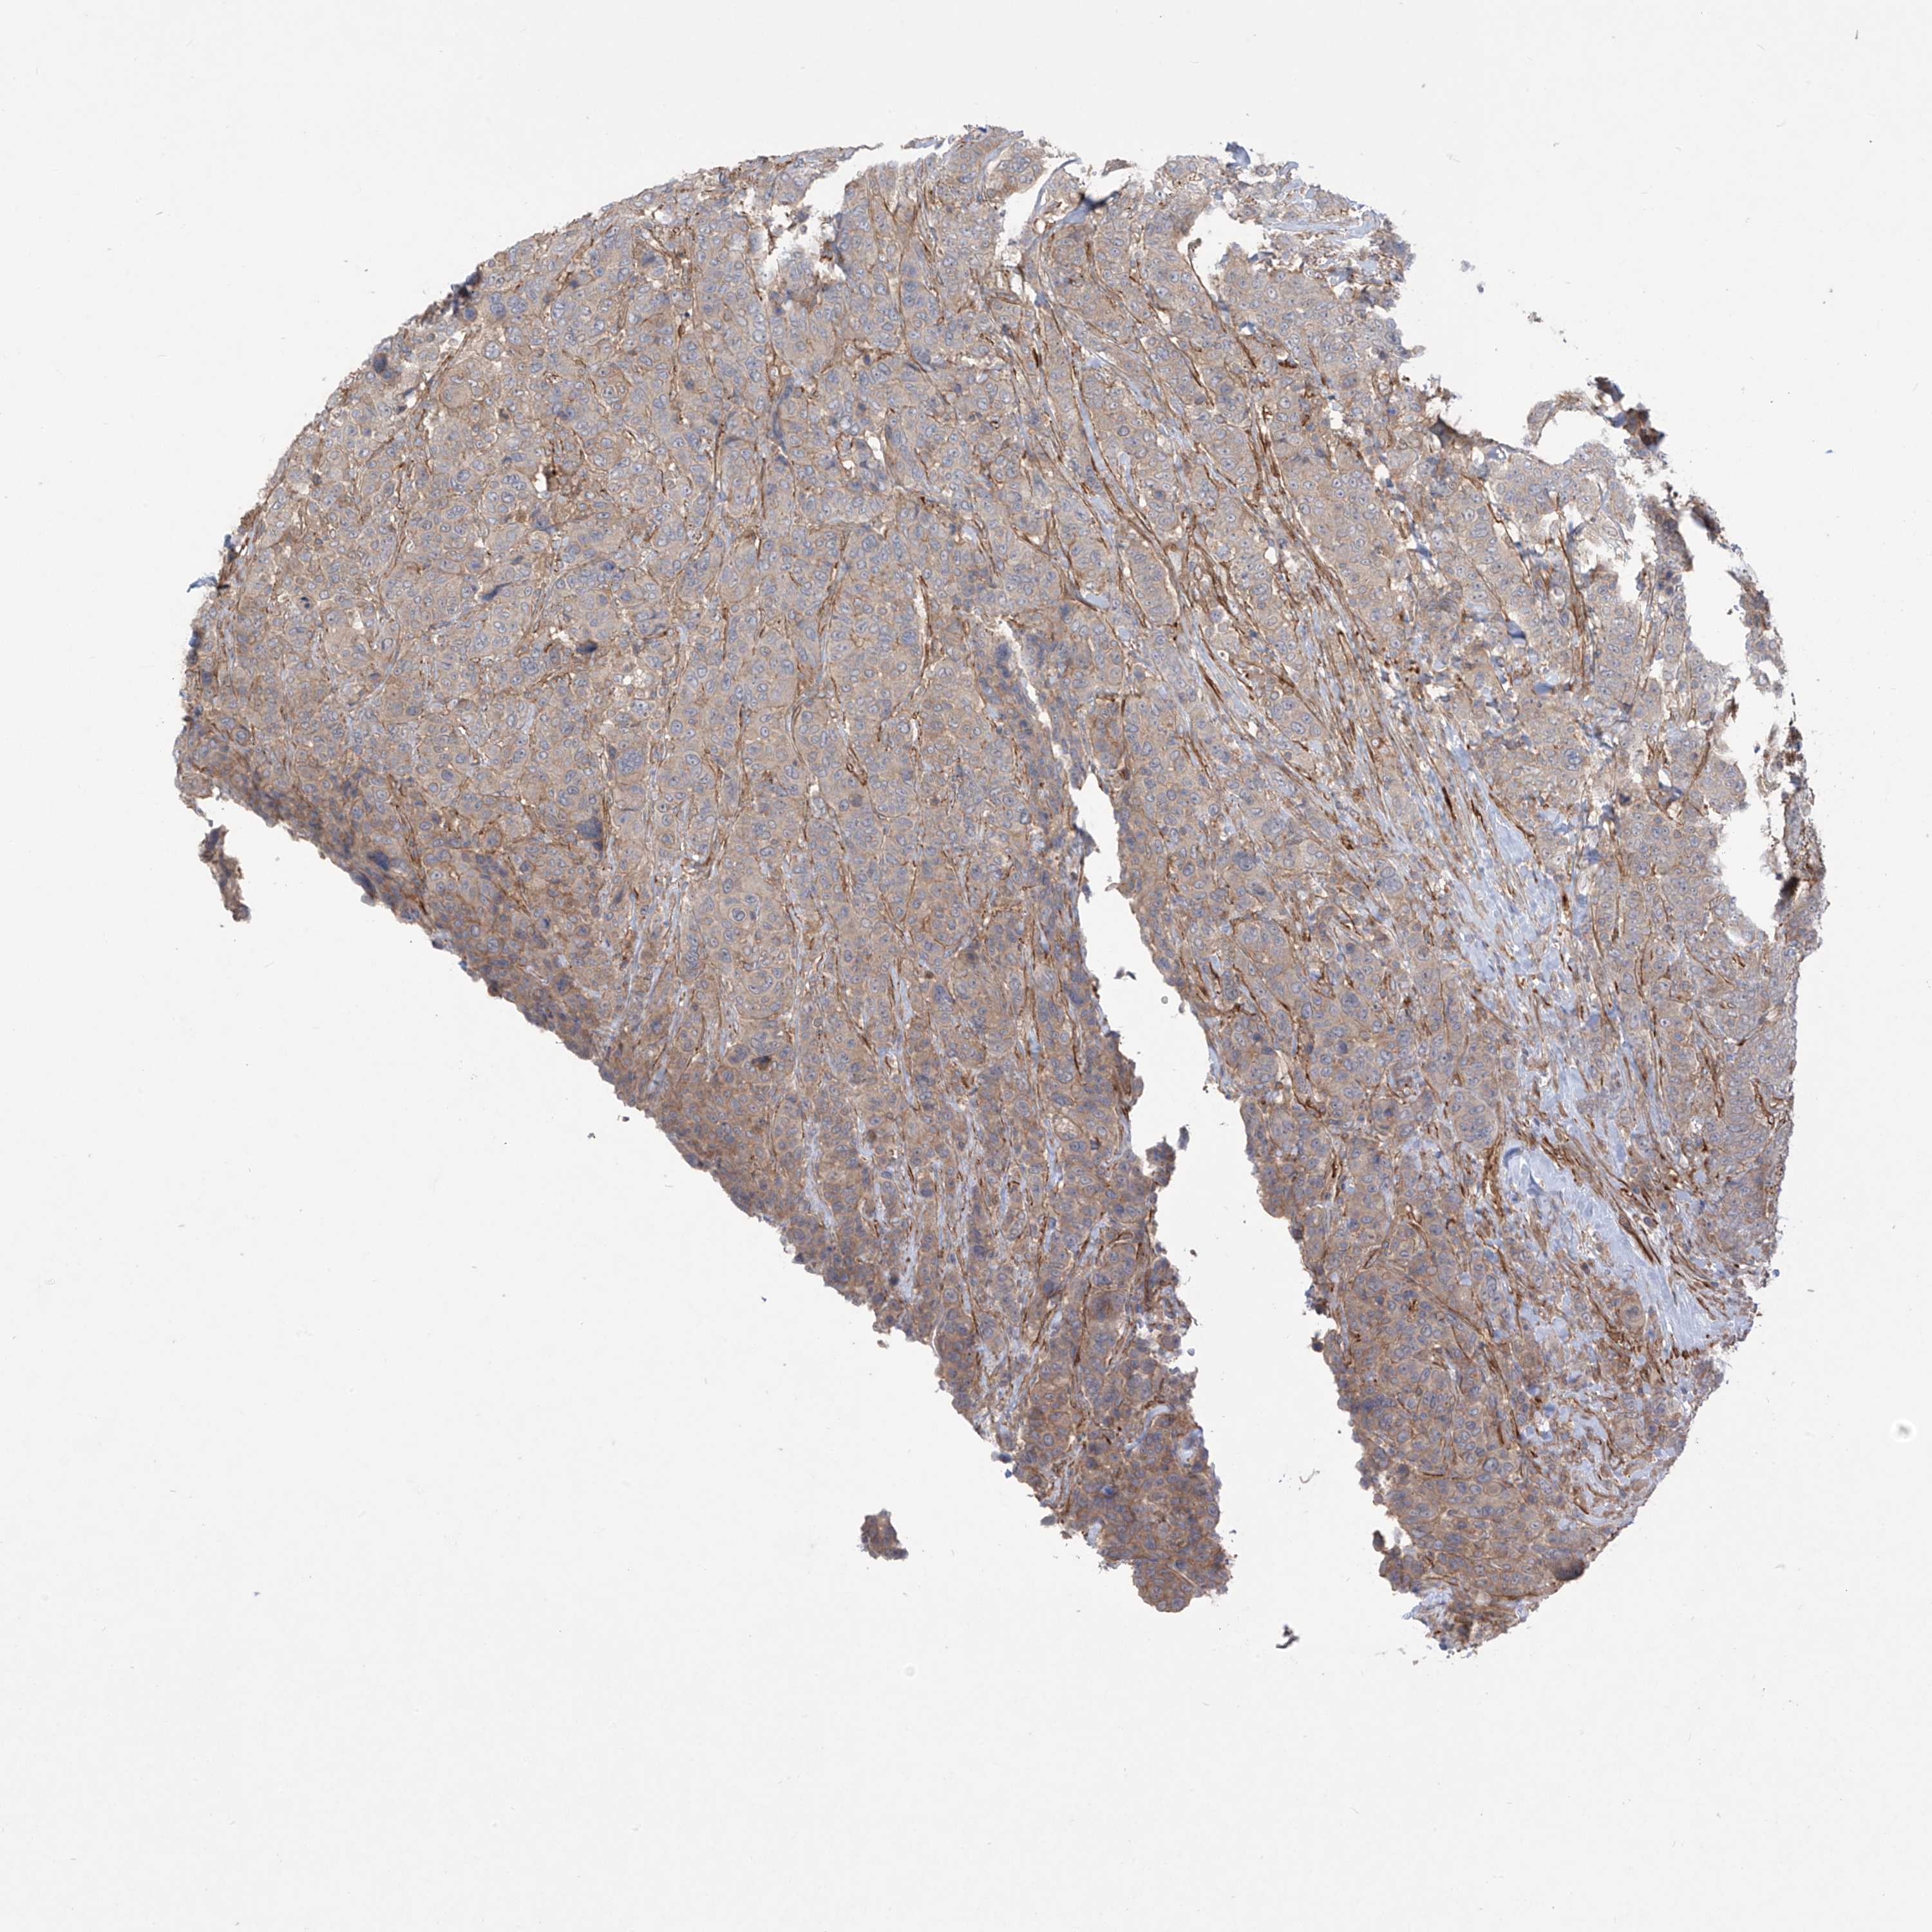

CANCER BREAST CANCER Show tissue menu

Breast cancer

Human cancer